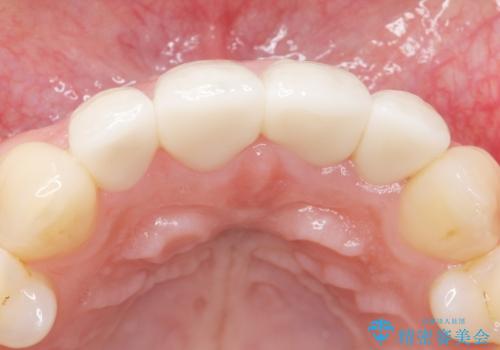

ご希望により、上の前歯4本のセラミッククラウンによる補綴治療を行いました。

綺麗な仕上がりに喜んで頂けました。

今後ホワイトニングを継続し天然歯をより白くしていく予定とのことで、クラウンのお色味は隣在歯よりやや白めにオーダーしております。

クラウンの種類:オールセラミッククラウン スタンダード